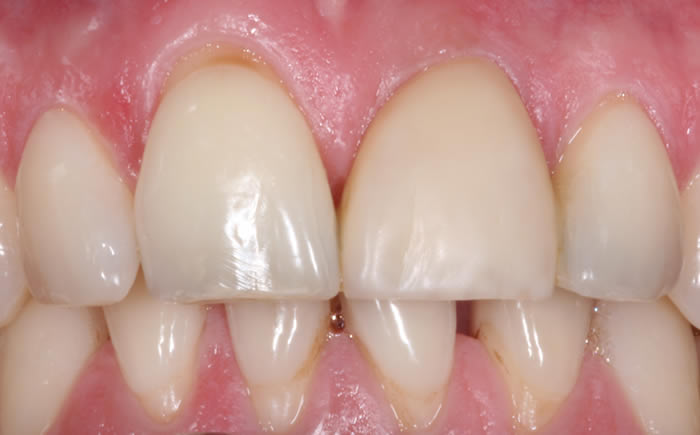

Before & After Gallery

More front teeth replaced by dental implants

Case Three (4 images)